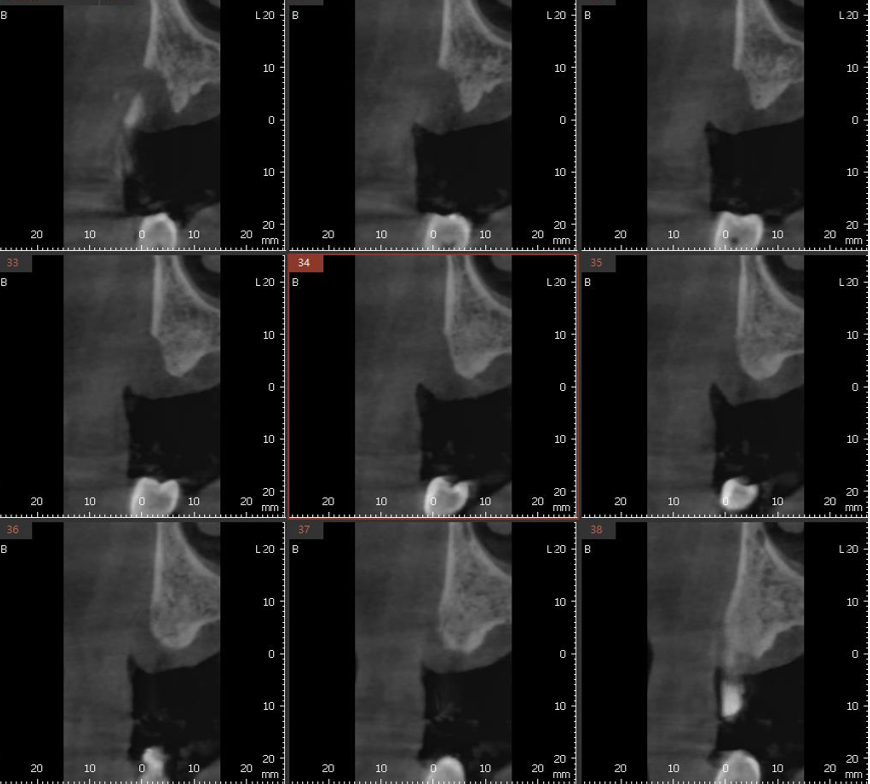

#14 부위의 CBCT 소견으로 협측이 심한 골흡수를 보이고 있으며 이로 인해 협측과 구개측 치조골은 심한 높이차를 보이고 있다 [그림 3].